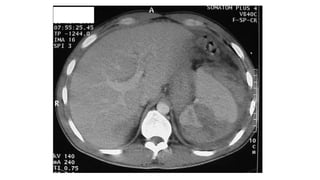

TAC

• Se debe de utilizar solo en el paciente estable.

• Evalúa el bazo y los órganos vecinos.

• Se utiliza contraste i.v., sin contraste puede no identificar un sangrado

intraparenquimatoso.

TAC • Se debede utilizar solo en el paciente estable. • Evalúa el bazo y los órganos vecinos. • Se utiliza contraste i.v., sin contraste puede no identificar un sangrado intraparenquimatoso.